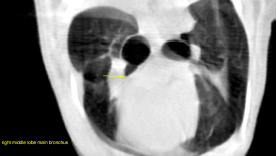

CT of the thorax, plain and post contrast- The main bronchus of the right middle lobe emerges in a ventral direction from the

bifurcation. The bronchus is dilated with an abrupt ending and collapsed lumen 5 mm

after its origin. There is regional lobar opacification and volume loss at this level. Air